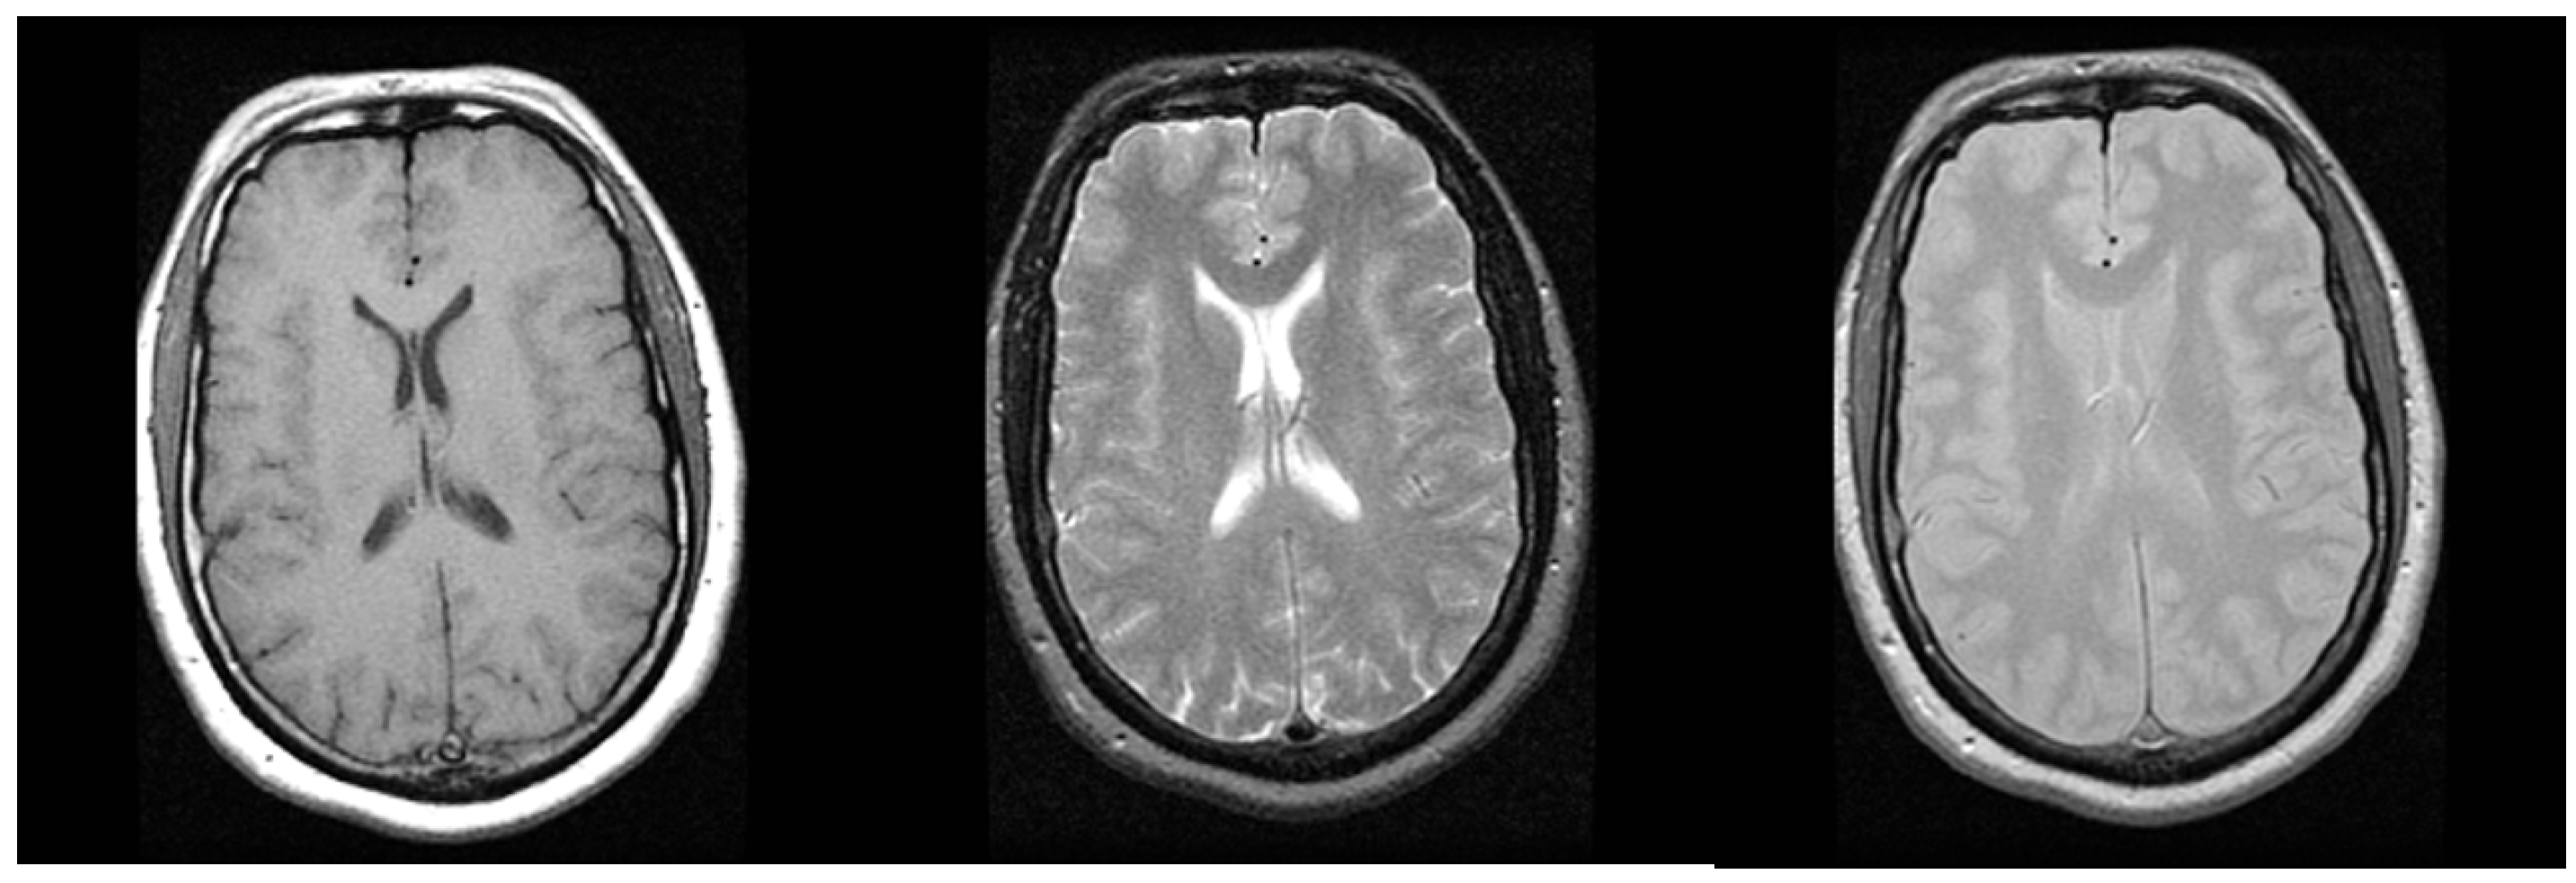

2.2. Magnetic Resonance Imaging

| TCGA-BRCA | MR Mammography | (256, 256, 148–160) | 12 |

| TCGA-GBM | MR T2 Flair Axial | (384, 512, 25–29) | 12 |